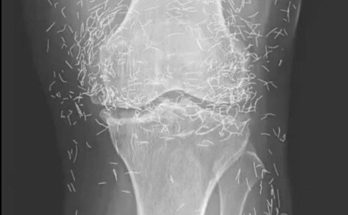

These are the consequences of sleeping with your c… See more A 65-year-old woman came to the clinic after experiencing months of chronic knee pain When a 65-year-old woman in …